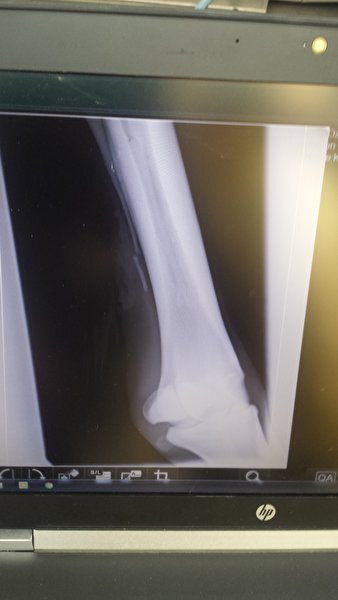

Icecrystal schreef:Mijn paard had precies dezelfde breuk als op jouw foto. Been bleef maar dik, verder niet kreupel.

Ik heb haar in Utrecht laten opereren voor rond de €1000,- . Een week boxrust en daarna de wei op. Na 2 weken wei was alles mooi slank en zijn we weer gaan opbouwen!

[ [url=m/uxbEy6.jpg]Afbeelding[/url] ]